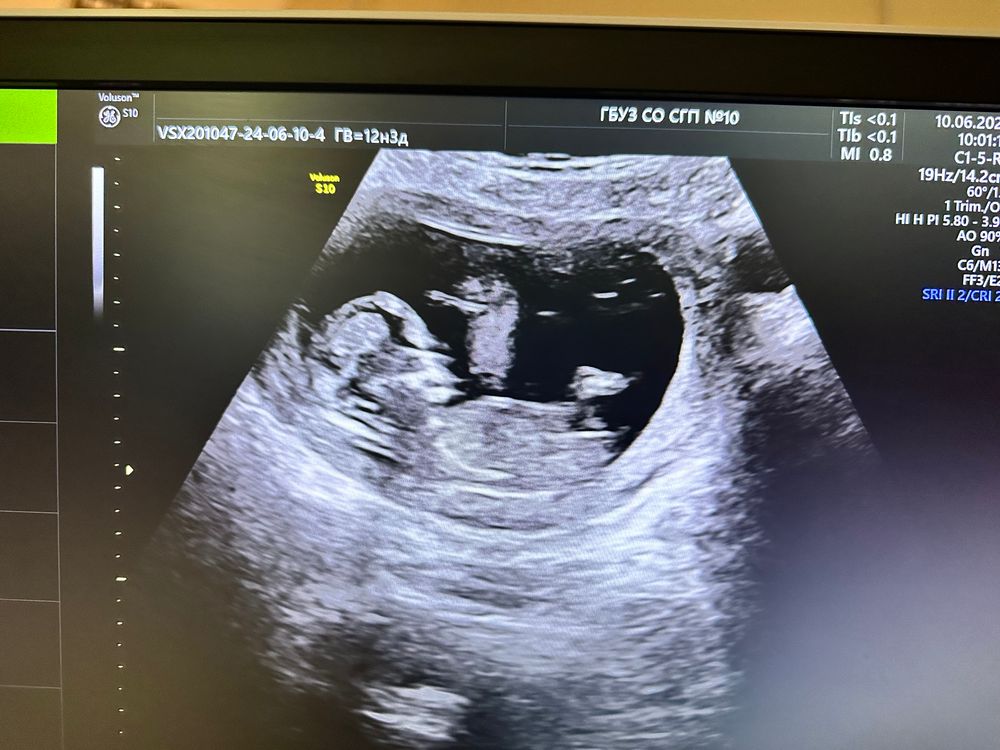

Первый скрининг, кого ждем?

На первом скриненге это чисто предложение попал или нет, вам не один узист не увидит точный пол, с 16 недели еще что-то можно усилить, в 12 нет.

Так вроде девочка

таню, полосочка - это бугорок или нога? 😄

таню, ну вот я тоже так подумала, а потом засомневалась за счет ракурса. Если как бы со спины, то не понятно, куда наклон

Не видно, ножкой закрывает